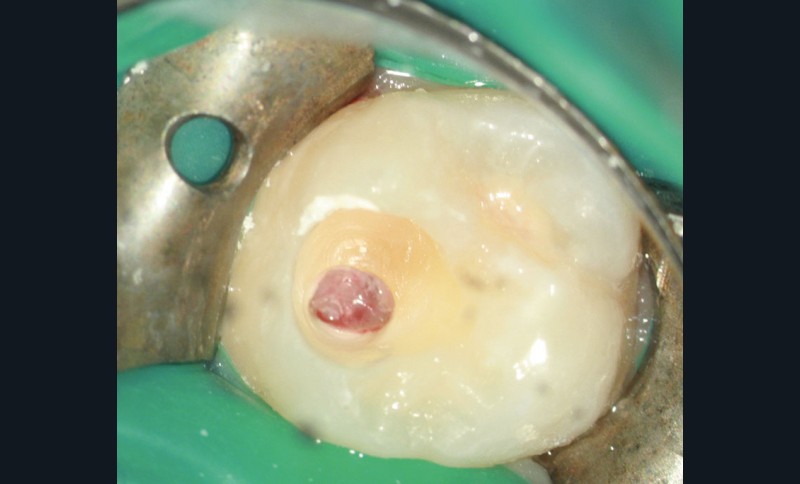

Dans les ouvrages et publications cliniques et scientifiques, une confusion linguistique s’est installée depuis plusieurs années à propos des termes utilisés pour décrire la protection pulpaire en odontologie. Cette différence est encore plus flagrante entre les spécialités. D’un point de vue purement sémantique, le « coiffage pulpaire » correspond à la mise en place d’un biomatériau au contact direct de la pulpe dentaire. L’exposition de ce tissu peut être d’origine traumatique (fracture coronaire par exemple), ou consécutive au curetage du tissu carieux au cours d’un soin conservateur, voire à une amputation volontaire (partielle ou totale) du tissu caméral (fig. 1).

Cependant, il est généralement considéré que le coiffage pulpaire direct ne concerne que l’exposition traumatique. Lorsqu’une éviction partielle du tissu est envisagée, on parle alors de « pulpotomie partielle », voire de pulpotomie camérale. Dans cette situation, le « coiffage pulpaire » est considéré comme une technique opératoire et non comme un concept thérapeutique, ce qui ne sera pas le cas dans la suite de cet article.

Qu’une amputation partielle soit effectuée ou non, un matériau est placé directement en contact avec le tissu pulpaire, et il s’agit donc bien d’un « coiffage pulpaire ». Dans les techniques opératoires, ce qui peut changer n’est que la préparation du tissu à recevoir le matériau, afin de le placer dans des conditions biologiques idéales pour induire une cicatrisation et une protection de sa vitalité dans le temps.